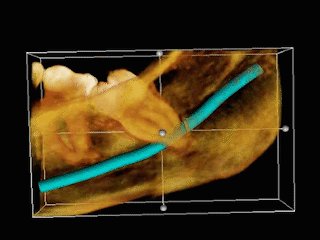

اما النوع الرابع وهو الأكثر حداثة بينهم ويسمى (Cone Beam CT (CBCT أو اشعة #الاسنان المقطعيه ثلاثية الأبعاد وتتميز بأننا نستطيع رؤية الانسجة بشكل ثلاثي الأبعاد وبدقة جيده مقارنة بالأنواع السابقة

وميزتها اننا نستطيع رؤيةوربط علاقة الانسجة ببعضها بشكل اقرب للواقع

واستخداماتها كثيرة:

-للتحضير قبل اي نوع من الجراحات (للسن او للزراعه الخ)

- في حال وجود خراج كبير

-للوصول لسبب الالم في حال لم تكن الاشعة الاخرى واضحة

-الكسور

-معرفة المكان الدقيق للأعضاء الحيوية مثلا عصب الفك

وهذا النوع يعتبر الأكثر تعريضاً للأشعة بين الأنواع الثلاثة ويعتمد على الوضوح المطلوب فالوضوح سيزيدمن كمية الاشعة،

ويجب ذكر ان تطور الأجهزة كبير فقد قلت كمية الاشعة عن اول جهاز تم اختراعه

ولاتستخدم بشكل يومي وإنما للحاجة

ومن عيوبها انها غير متوفرة في كثير من المراكز وتعتبر مكلفة